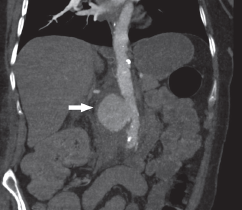

Imágenes y Cirugía

Natalia González Alcolea, María Dolores Chaparro Cabezas, Félix Martínez Arrieta, Victor Sánchez Turrión